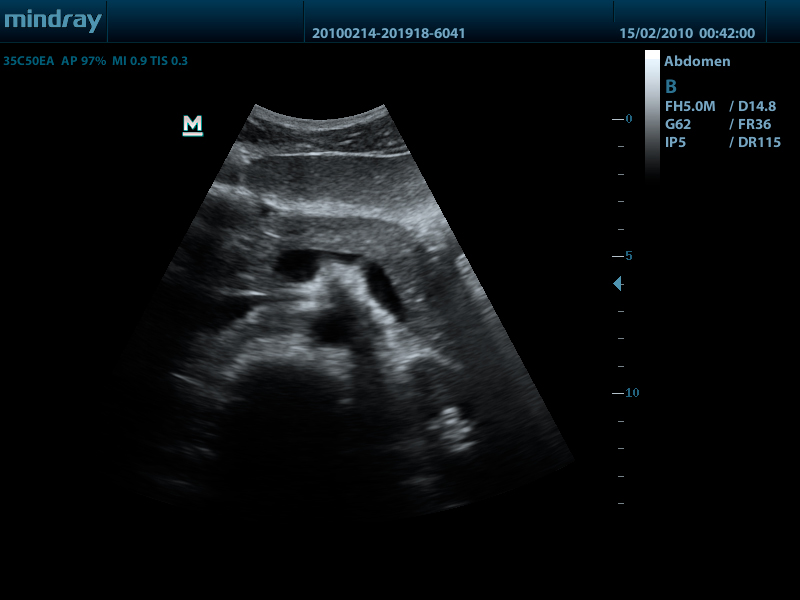

- Конвексный датчик 35C50EA, 1.7 - 6.0 МГц, радиус кривизны 50 мм